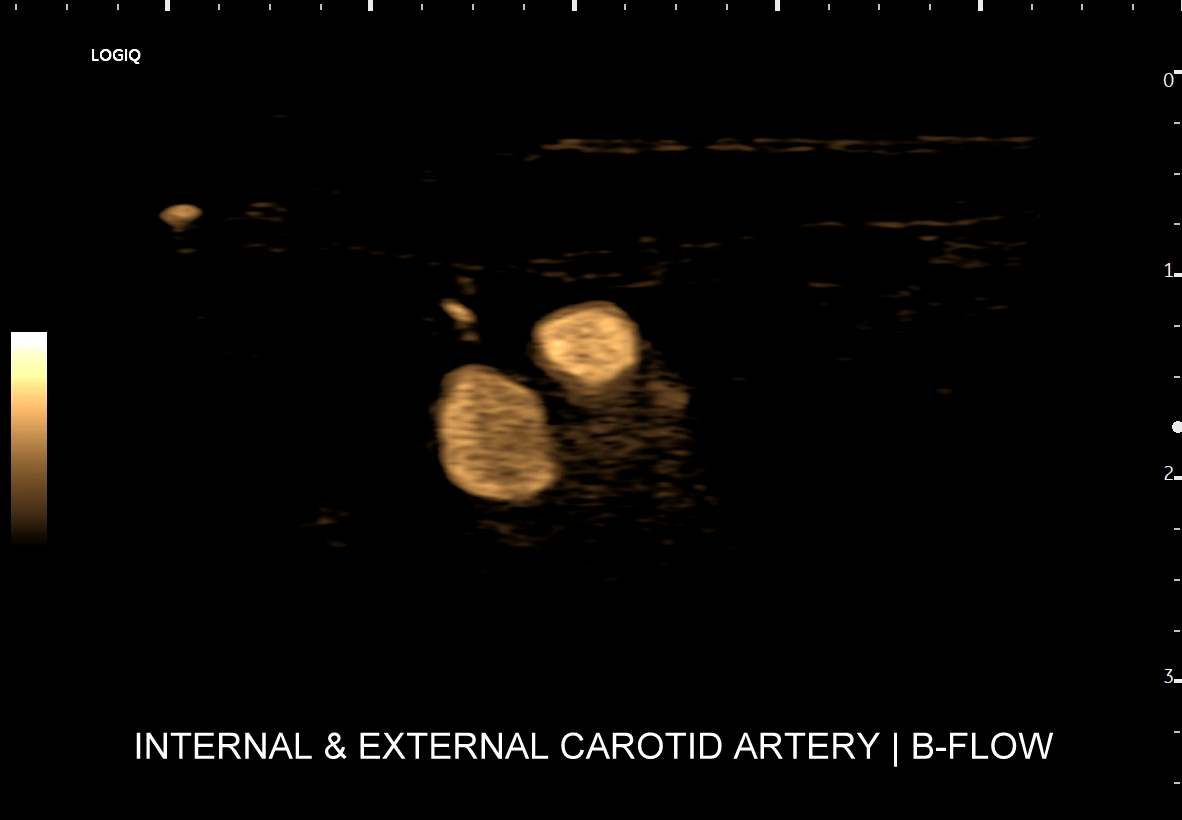

Tryb B-flow wyjątkowo korzystnie sprawdza się także przy badaniu wnętrza dużych i średnich naczyń. Otóż umożliwia on pewne zobrazowanie drożności naczynia, umożliwia wykazanie obecności / lokalizacji naczynia przy niesprzyjających warunkach obrazowania w trybie B, a poza tym uzyskiwane w omawianym trybie obrazy zarysów błony wewnętrznej naczyń (np. tętniczych blaszek miażdżycowych, skrzeplin przyściennych, zmian w przebiegu dysplazji włóknisto-mięśniowej, czy zapaleń tętnic) charakteryzują się wysoką rozdzielczością i kontrastowością. Skany dużych naczyń w trybie B-flow przypominają wręcz te uzyskiwane w klasycznej angiografii opartej o promieniowanie rentgenowskie. B-flow wykorzystywany może być praktycznie i rutynowo do obrazowania naczyń szyi i kończyn, naczyń wątroby, naczyń trzewnych, nerkowych oraz dużych naczyń brzusznych.